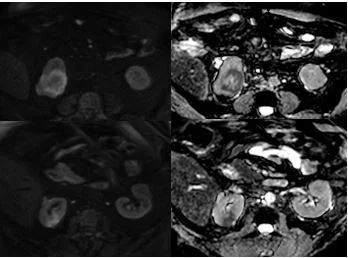

Subsequent MRI showed these lesions were larger, and consistent with lung cancer metastasis. In many instances, Spectral CT is like DWI in body imaging: it can really make detection of lesions simple, and stop you from missing something that may be obvious in retrospect.

MRI (DWI b800 with ADC map): lesions are larger. Spectral CT is like DWI in some ways, significantly enhances detection of lesions in body imaging.